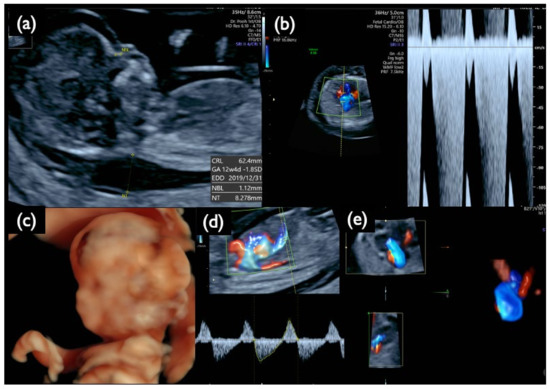

| Chromosome 18 relevant mosaicism | Mo5 | 13 + 5 | XX,+18 Mosaicism | T18 (56%) | 47,XX,+18/46,XX (44%/56%) | – | – | T18 Negative | 2.09 | + | 8.3 | Increased NT, GE moderate, Small NB, Micrognathia, Lowset ear, T18 like profile, Wrist contracture bilateral, Cardiomegaly, Large VSD, TR severe, MR severe, Stomach invisible, Hyperechoic bowel, DV reversed flow, SUA, Umb.A.reverse, T18 is strongly suspected, |

| NC2 | 12w2d | CVS | 22.8 | 47,XY,+21 | No Call | + | 5.3 | Increased NT, Small CH, GE, bilateral, PE, NB defect, Micrognathia, Lowset ear, s/o Large VSD, TR moderate, Levocardia, RV>LV, Hyperechoic bowel, DV reverse, Short FL, T 21 is strongly suspected |

| NC3 | 13w1d | CVS | 25.8 | 47,XY,+18 | No Call | + | 10.6 | Increased NT, CH, GE, Small NB, Micrognathia, Lowset ear, Hypoplastic ear, Cleft lip (left), Maxillary gap, Mild wrist contracture bilateral, RV>LV, TR, DV reverse, Bradycardia, T18 is strongly suspected |